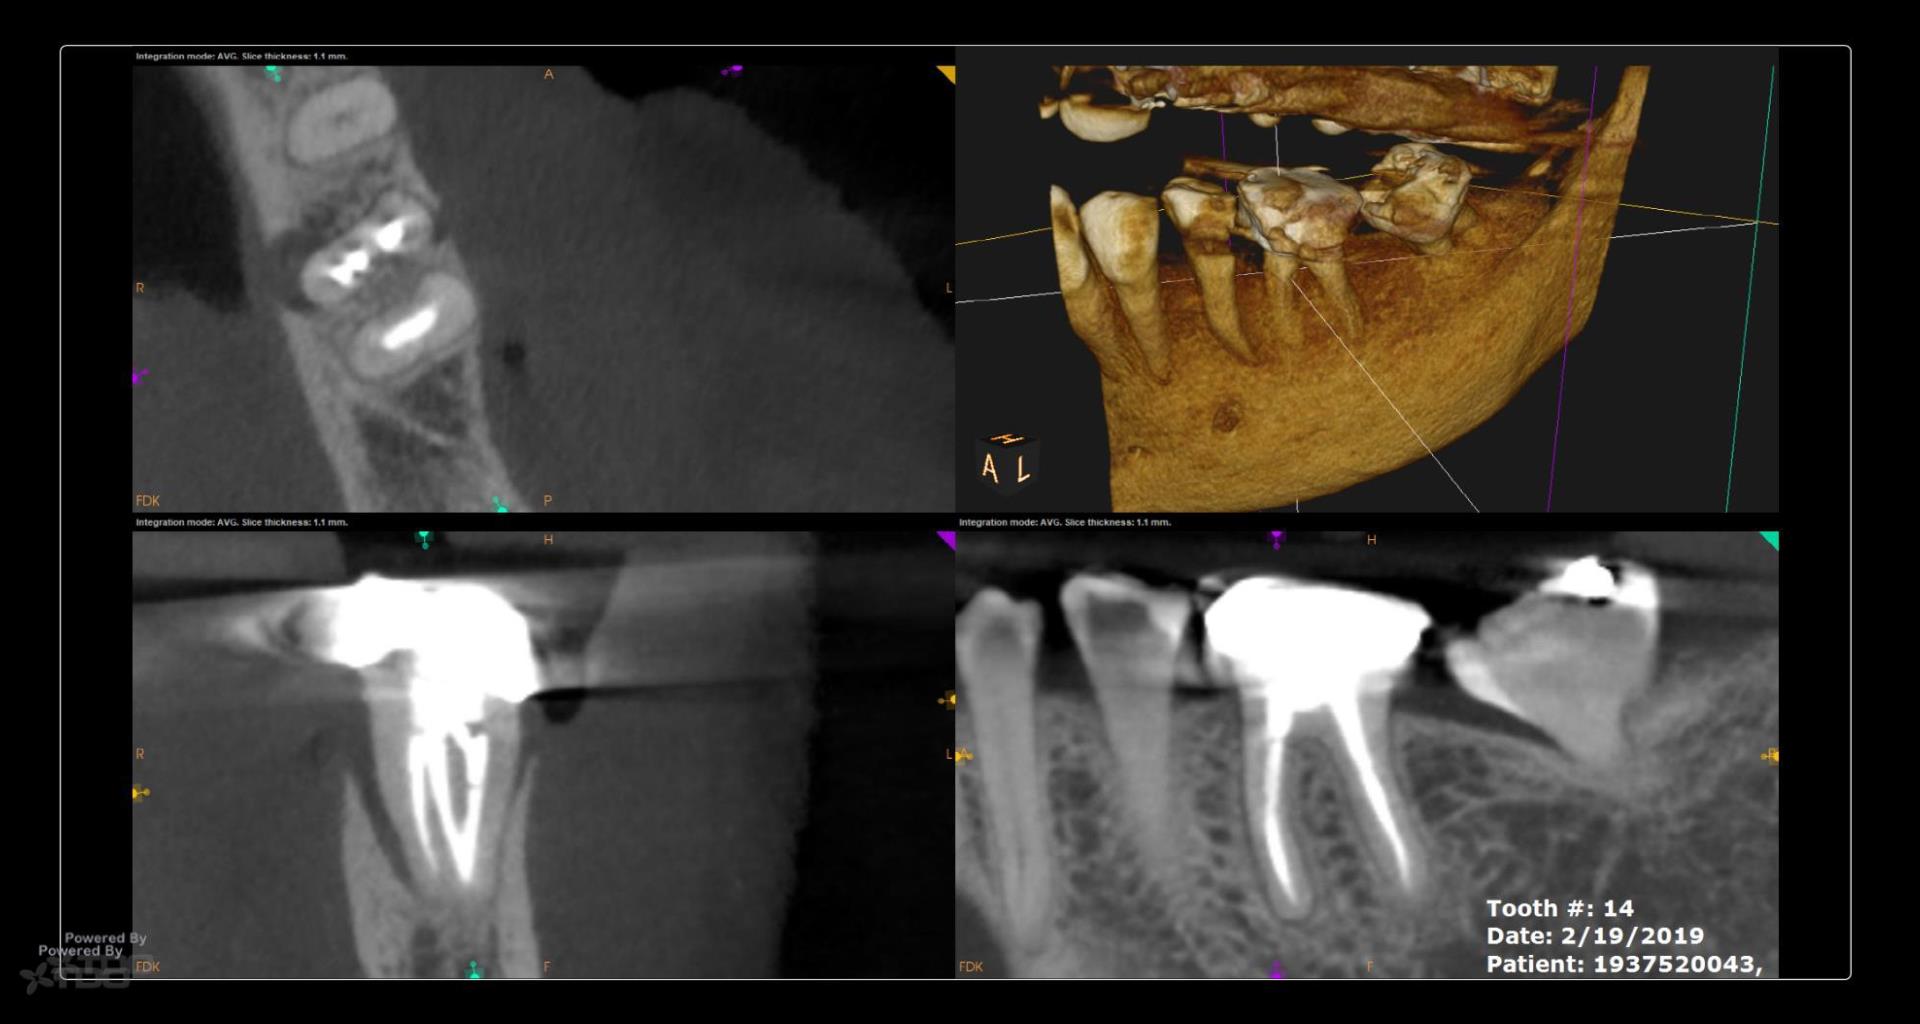

OK biofilm mavens…….I am ready to photograph the “Riccucci-style” processing of the apical distal root (#3)….. what do people think this will show? The same results Riccucci gets? Think before you answer….. gbc

Fascinating case! If you’re doing Ricucci-style processing on the apical distal root, I’d expect to see similar patterns of biofilm penetration—especially if there was a history of chronic infection.